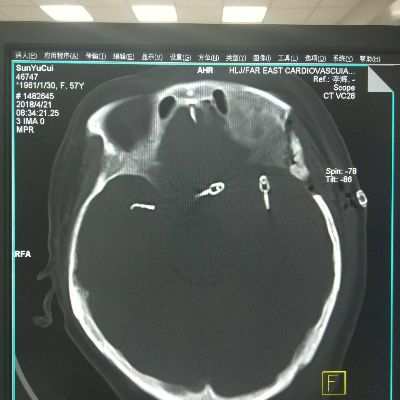

双侧梗死?什么原因?

右侧大脑中分叉有个动脉瘤,警惕破裂。

单纯支架取栓,没用中间导管?